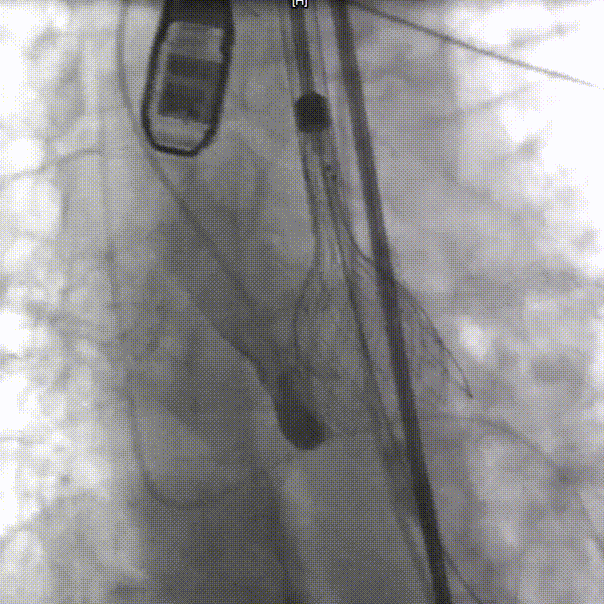

输送器过弓

整体入路造影,右侧细,走左侧为主入路,左侧用外周球囊预扩后送大鞘

20mm球囊预扩,球囊下滑

再次预扩,球囊上跳

瓣下3mm定位

释放到工作位,瓣下5mm左右

缓慢脱钩